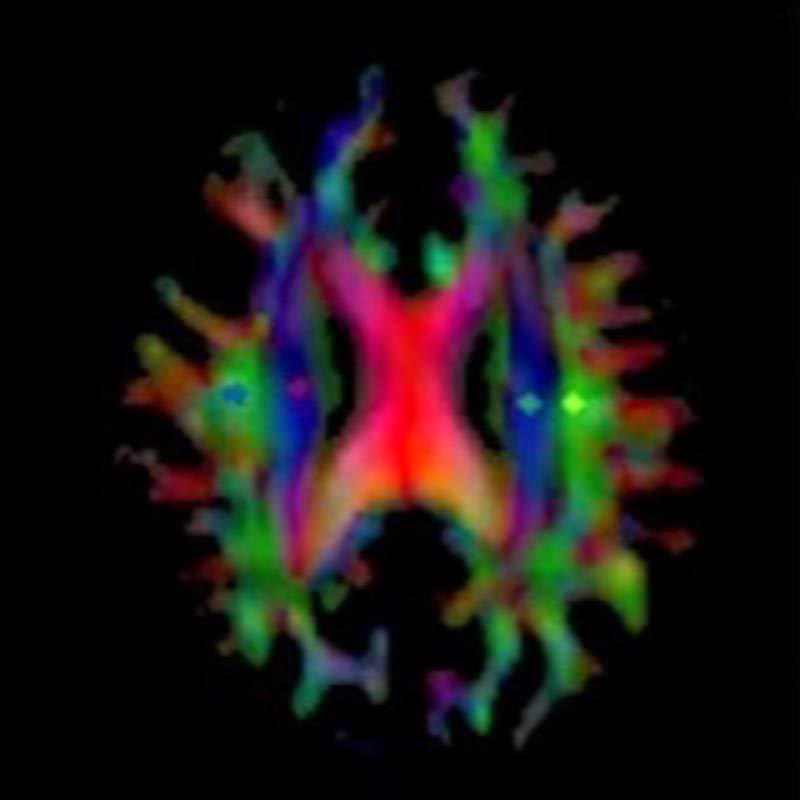

A major driver of nerve cell damage in AD is the accumulation of amyloid-β (Aβ) in the brain. In people without the disease, a network known as the glymphatic system circulates cerebrospinal fluid along the spaces surrounding arteries and into brain tissue. There, this fluid mixes with interstitial fluid to help remove metabolic waste products, including Aβ. The name "glymphatic system" comes from the involvement of glial cells in this process.

Lecanemab, which was recently approved as a therapeutic option, is intended to lower Aβ levels. To study its effects, the Osaka Metropolitan University team examined the glymphatic system in patients both before and after lecanemab treatment, using the DTI-ALPS index to measure changes.